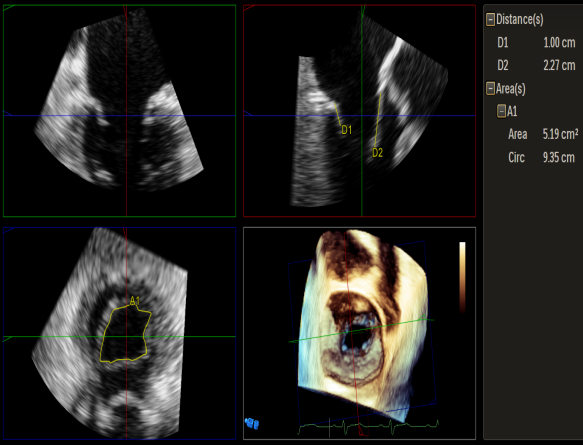

Qlab软件勾画估测瓣口面积约:5.19cm²

3D视图下大鞘位置及长度测量